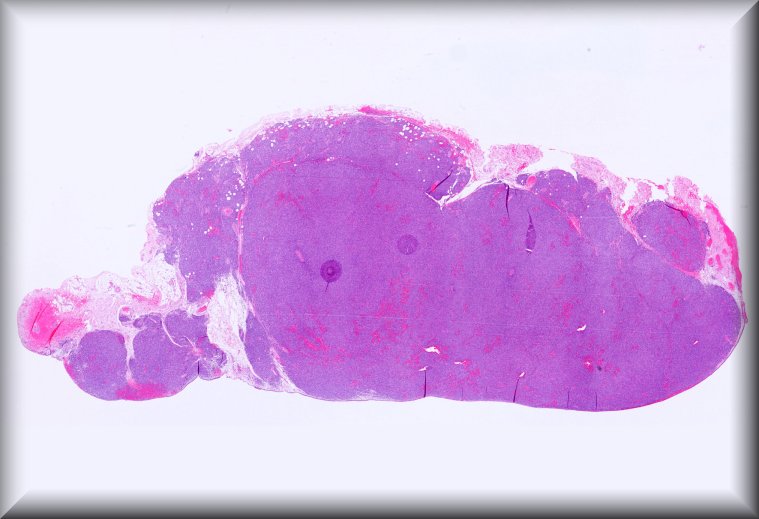

Patricia Chévez Barrios (Houston): 2 year-old-boy with history of group D unilateral retinoblastoma s/p systemic chemotherapy, cryotherapy and intravirteous chemotherapy. Enucleated for progressive disease. |